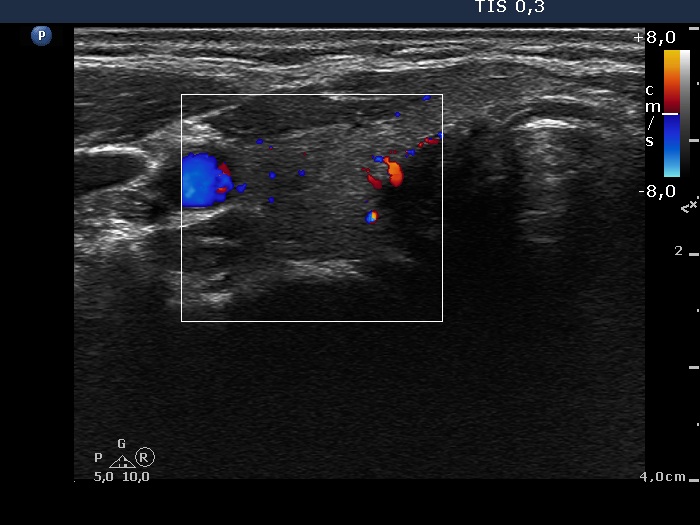

Subacute granulomatous de Quervain's thyroiditis - Case 6.

Five months after initial investigation (ultrasonographic picture 4)

Right lobe, horizontal view, color Doppler mode. The vascularization is already decreased.